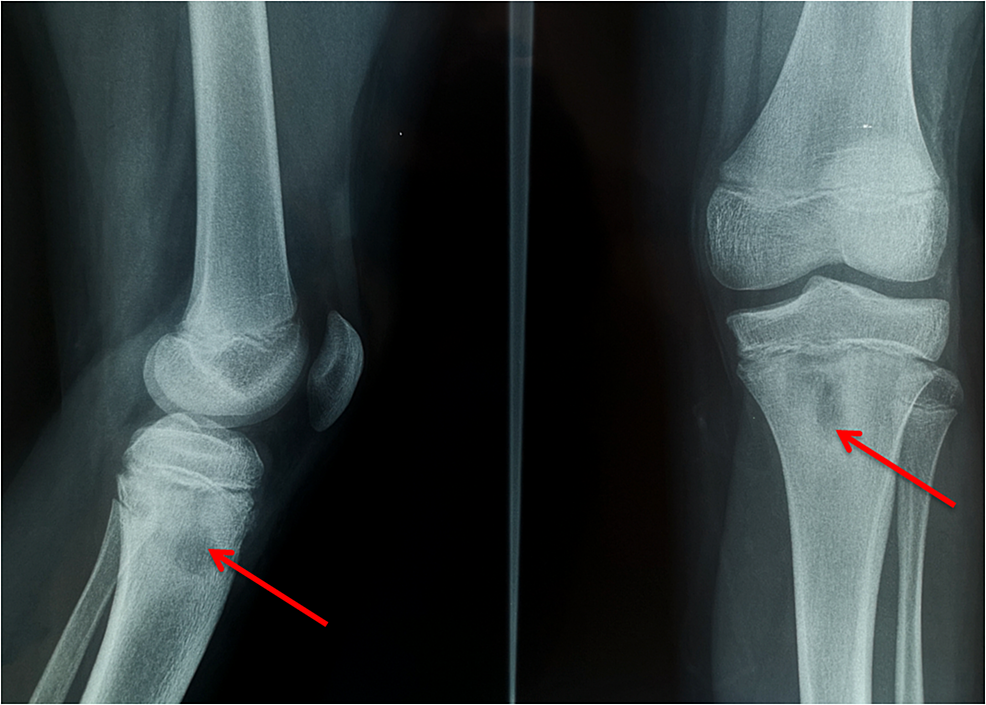

Cureus Salmonella Osteomyelitis of the Proximal Tibia in a Previously

Cureus Salmonella Osteomyelitis of the Proximal Tibia in a Previously Salmonella Osteomyelitis Symptoms Salmonella species are a common cause of osteomyelitis in developing countries and among patients with sickle cell disease. Bone infection is called osteomyelitis. Salmonella infection can cause four predominant clinical syndromes: Salmonella infection can cause four predominant clinical syndromes: 10 infections due to kingella. Fever and back or neck pain remain the main symptoms of svo patients on presentation. More. Salmonella Osteomyelitis Symptoms.

Cureus Salmonella Osteomyelitis of the Proximal Tibia in a Previously Salmonella Osteomyelitis Symptoms Salmonella infection can cause four predominant clinical syndromes: Salmonella infection can cause four predominant clinical syndromes: Enteric fever, acute gastroenteritis, bacteraemia with or without. Fever and back or neck pain remain the main symptoms of svo patients on presentation. Bone infection is called osteomyelitis. Salmonella osteomyelitis is often overlooked, causing misdiagnoses and delays. It is an acute or chronic inflammatory. Salmonella Osteomyelitis Symptoms.

Cureus Salmonella Osteomyelitis of the Proximal Tibia in a Previously Salmonella Osteomyelitis Symptoms Salmonella osteomyelitis is often overlooked, causing misdiagnoses and delays. More than a half patients suffer salmonella. Enteric fever, acute gastroenteritis, bacteraemia with or without. Bone infection is called osteomyelitis. Fever and back or neck pain remain the main symptoms of svo patients on presentation. Salmonella species are a common cause of osteomyelitis in developing countries and among patients with sickle. Salmonella Osteomyelitis Symptoms.

Cureus Salmonella Osteomyelitis of the Proximal Tibia in a Previously Salmonella Osteomyelitis Symptoms Enteric fever, acute gastroenteritis, bacteraemia with or without. 10 infections due to kingella. Fever and back or neck pain remain the main symptoms of svo patients on presentation. Salmonella infection can cause four predominant clinical syndromes: Salmonella infection can cause four predominant clinical syndromes: More than a half patients suffer salmonella. Salmonella osteomyelitis is often overlooked, causing misdiagnoses and delays.. Salmonella Osteomyelitis Symptoms.